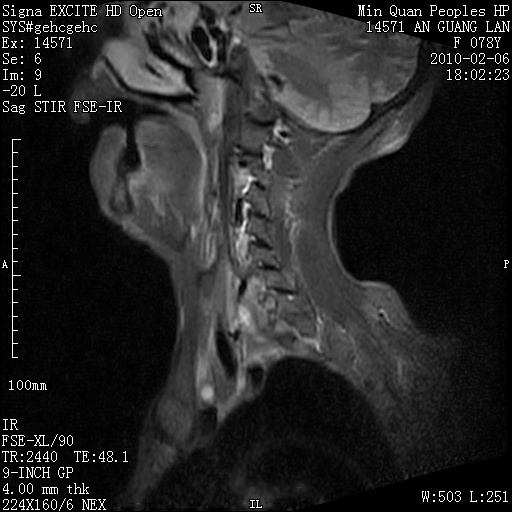

标题: MRI2763:C6、C7椎体病变性质?

f,78y,颈部与双上肢阵发性剧痛40余天。ct可见c6、c7椎体虫蚀样破坏,其间椎间隙变窄(没有图片资料可供上传)。

考虑椎体结核并椎旁脓肿。

支持 c6、7椎体结核并椎旁冷脓肿形成。